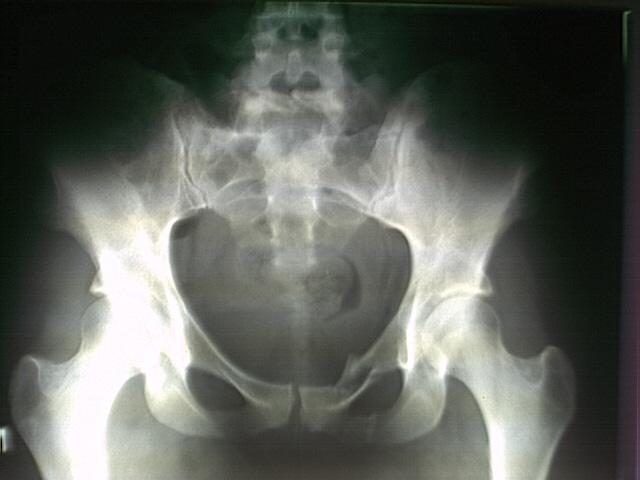

Рентгенограмма тазобедренного сустава прямая проекция

Больной П., 81 года, со слов родственников и больного, упал со стула. Сразу почувствовал резкую боль в правом тазобедренном суставе, самостоятельно встать не смог. Больной предъявляет жалобы на боль в области тазобедренного сустава, которая локализуется под пупартовой связкой. Боль усиливается при пальпации.

Из анамнеза выявлено, что больной страдает гипертонической болезнью. Объективно: лежит в постели, правая нижняя конечность ротирована кнаружи. Больной не в состоянии поднять и удержать выпрямленную в коленном суставе ногу. При попытке поднять поврежденную конечность пятка скользит по поверхности кровати (положительный симптом «прилипшей пятки»), нога отечна, несколько укорочена по сравнению с другой.

П

ри

попытке произвести пассивные и активные

движения, а так же при осевой нагрузке

бедра или шейки (поколачивание по пятке

выпрямленной конечности или по области

большого вертела) боль резко усиливается.

Отмечается усиление пульсации бедренной

артерии под пупартовой связкой

(положительный симптом С. С. Гирголава).

Большой вертел находится выше линии

Розер-Нелатона, выявляется нарушение

равнобедренности треугольника Бриана.

АД 180/90 мм. рт. ст., тоны сердца глухие,

экстрасистолия. Со стороны органов

брюшной полости изменений нет.